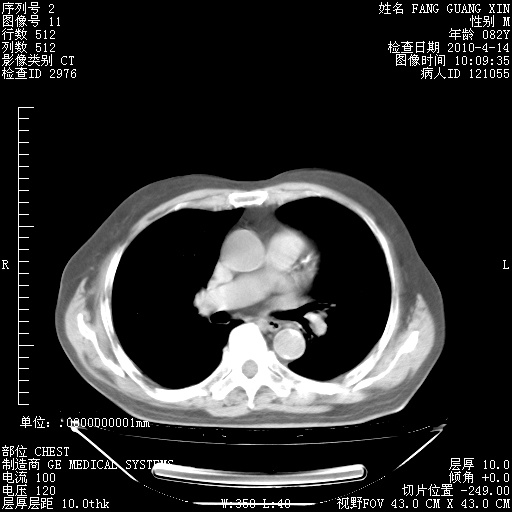

4月14日肺部CT

楼主| 发表于 2010-4-28 16:47 | 显示全部楼层

31.JPG

32.JPG

33.JPG

34.JPG